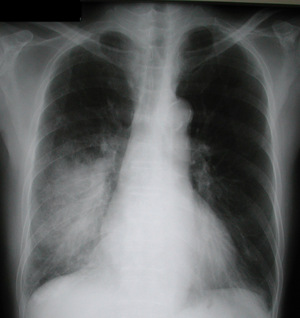

Пневмония на снимке, в частности затемнения, характеризуются следующим образом:

- Распространённые. Визуализируют в пределах одного сегмента.

- Субтотальные. Затемнение большей части поля органа или нескольких сегментов.

- Тотальные. Патологический процесс охватывает всю область лёгочной ткани. Сильная пневмония слева

Крупозная пневмония на рентгене

При слиянии отдельных очагов воспаления легочной ткани возникает крупозная пневмония. Фото рентгеновского снимка, сделанного при этой форме заболевания, наглядно показывает отличия.

Как правило, при крупозной форме воспаления легких поражается одна или несколько долей легких сразу. Это создает серьезную угрозу жизни пациента.

На рентгене крупозная форма болезни проявляется следующими признаками:

- Ярко выраженные крупные тени, затрагивающие доли легкого целиком. Могут быть поражены оба легкого.

- Средостение смещается в сторону наиболее воспаленного легкого.

- На куполах диафрагмы отчетливо видны признаки деформации.

- Рисунок легочной ткани может не просматриваться.

Крупозная пневмония легче всего выявляется при рентгенологическом исследовании. Тем не менее для постановки точного диагноза врачи предпочитают делать рентгеновские снимки в двух проекциях. Это дает им возможность определить число пораженных воспалением сегментов органа и определить состояние средостения.